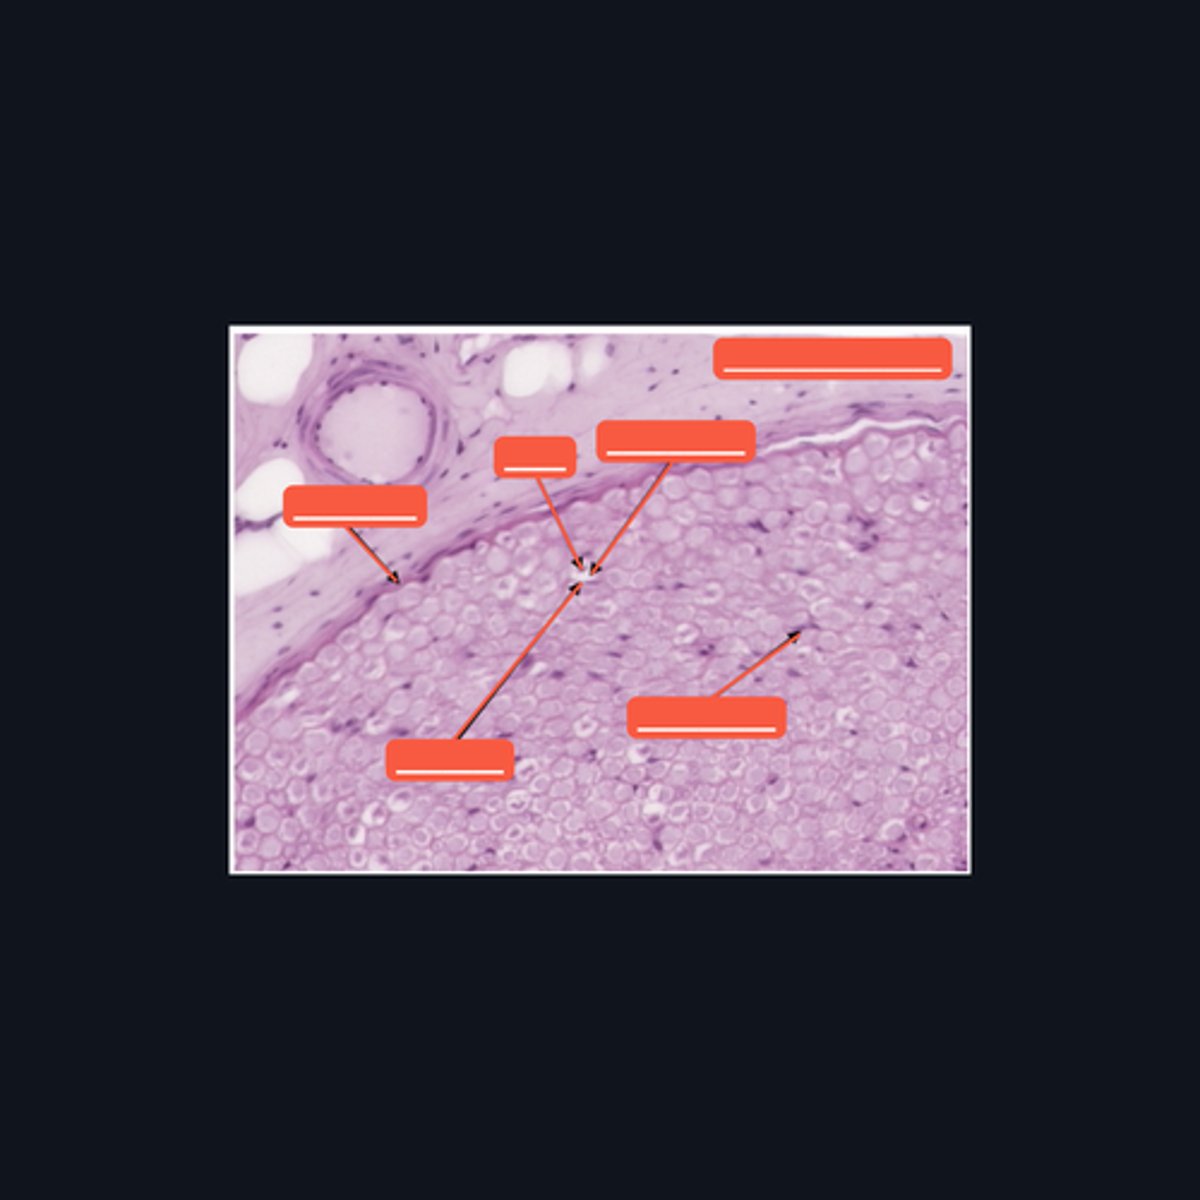

Dorsal root ganglion and nervous tissue

Identify the specific structure given in the image, as well as the type of tissue predominating in the structure.

(top to bottom)

Somatic sensory neurons

Capsule

Identify the structures of the dorsal root ganglion. Be as specific as possible.

(top to bottom)

Cell body

Satellite cell

Nucleus

Nucleolus

Nerve fibers

Identify the parts of the spinal ganglion in high magnification.

False, pseudounipolar

T or F: The neurons that congregate in this structure is multipolar.

(bottom to top)

Capsule

Ganglion Cell

Satellite cell

Nerve fibers

Nucleolus

Nucleus

Nissl Granules

Identify the structures of a sympathetic ganglion.

Multipolar, autonomic motor neurons

What kind of motor neurons are present in this structure?

Dense Irregular Connective Tissue

What kind of tissue is the capsule of a spinal ganglion made up of? Be specific.